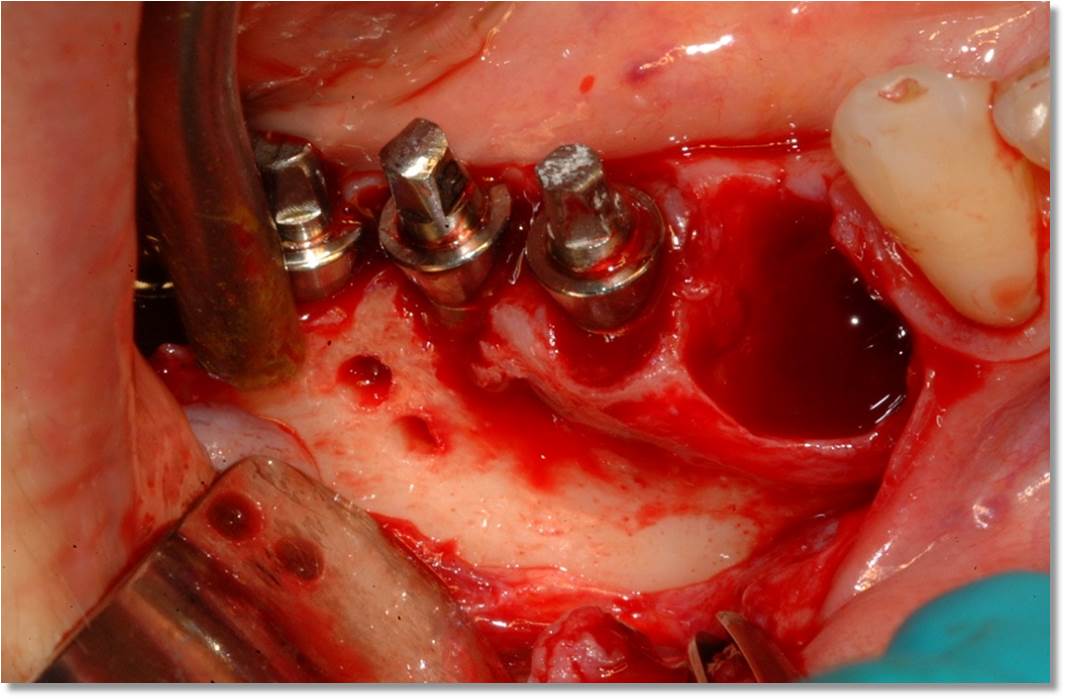

Questa tecnica viene utilizzata dagli anni '80 e si è sempre più imposta nello sport e nella vita quotidiana. Solo recentemente Cavallini e Leghissa hanno pensato di applicarla al post chirurgico odontoiatrico osservando risultati davvero incoraggianti.